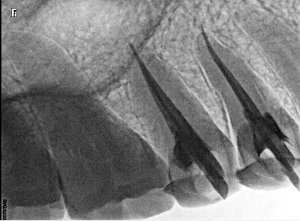

Welcome to our gallery

See how our company transforms ideas into reality. This gallery is a visual testament to our work and achievements.